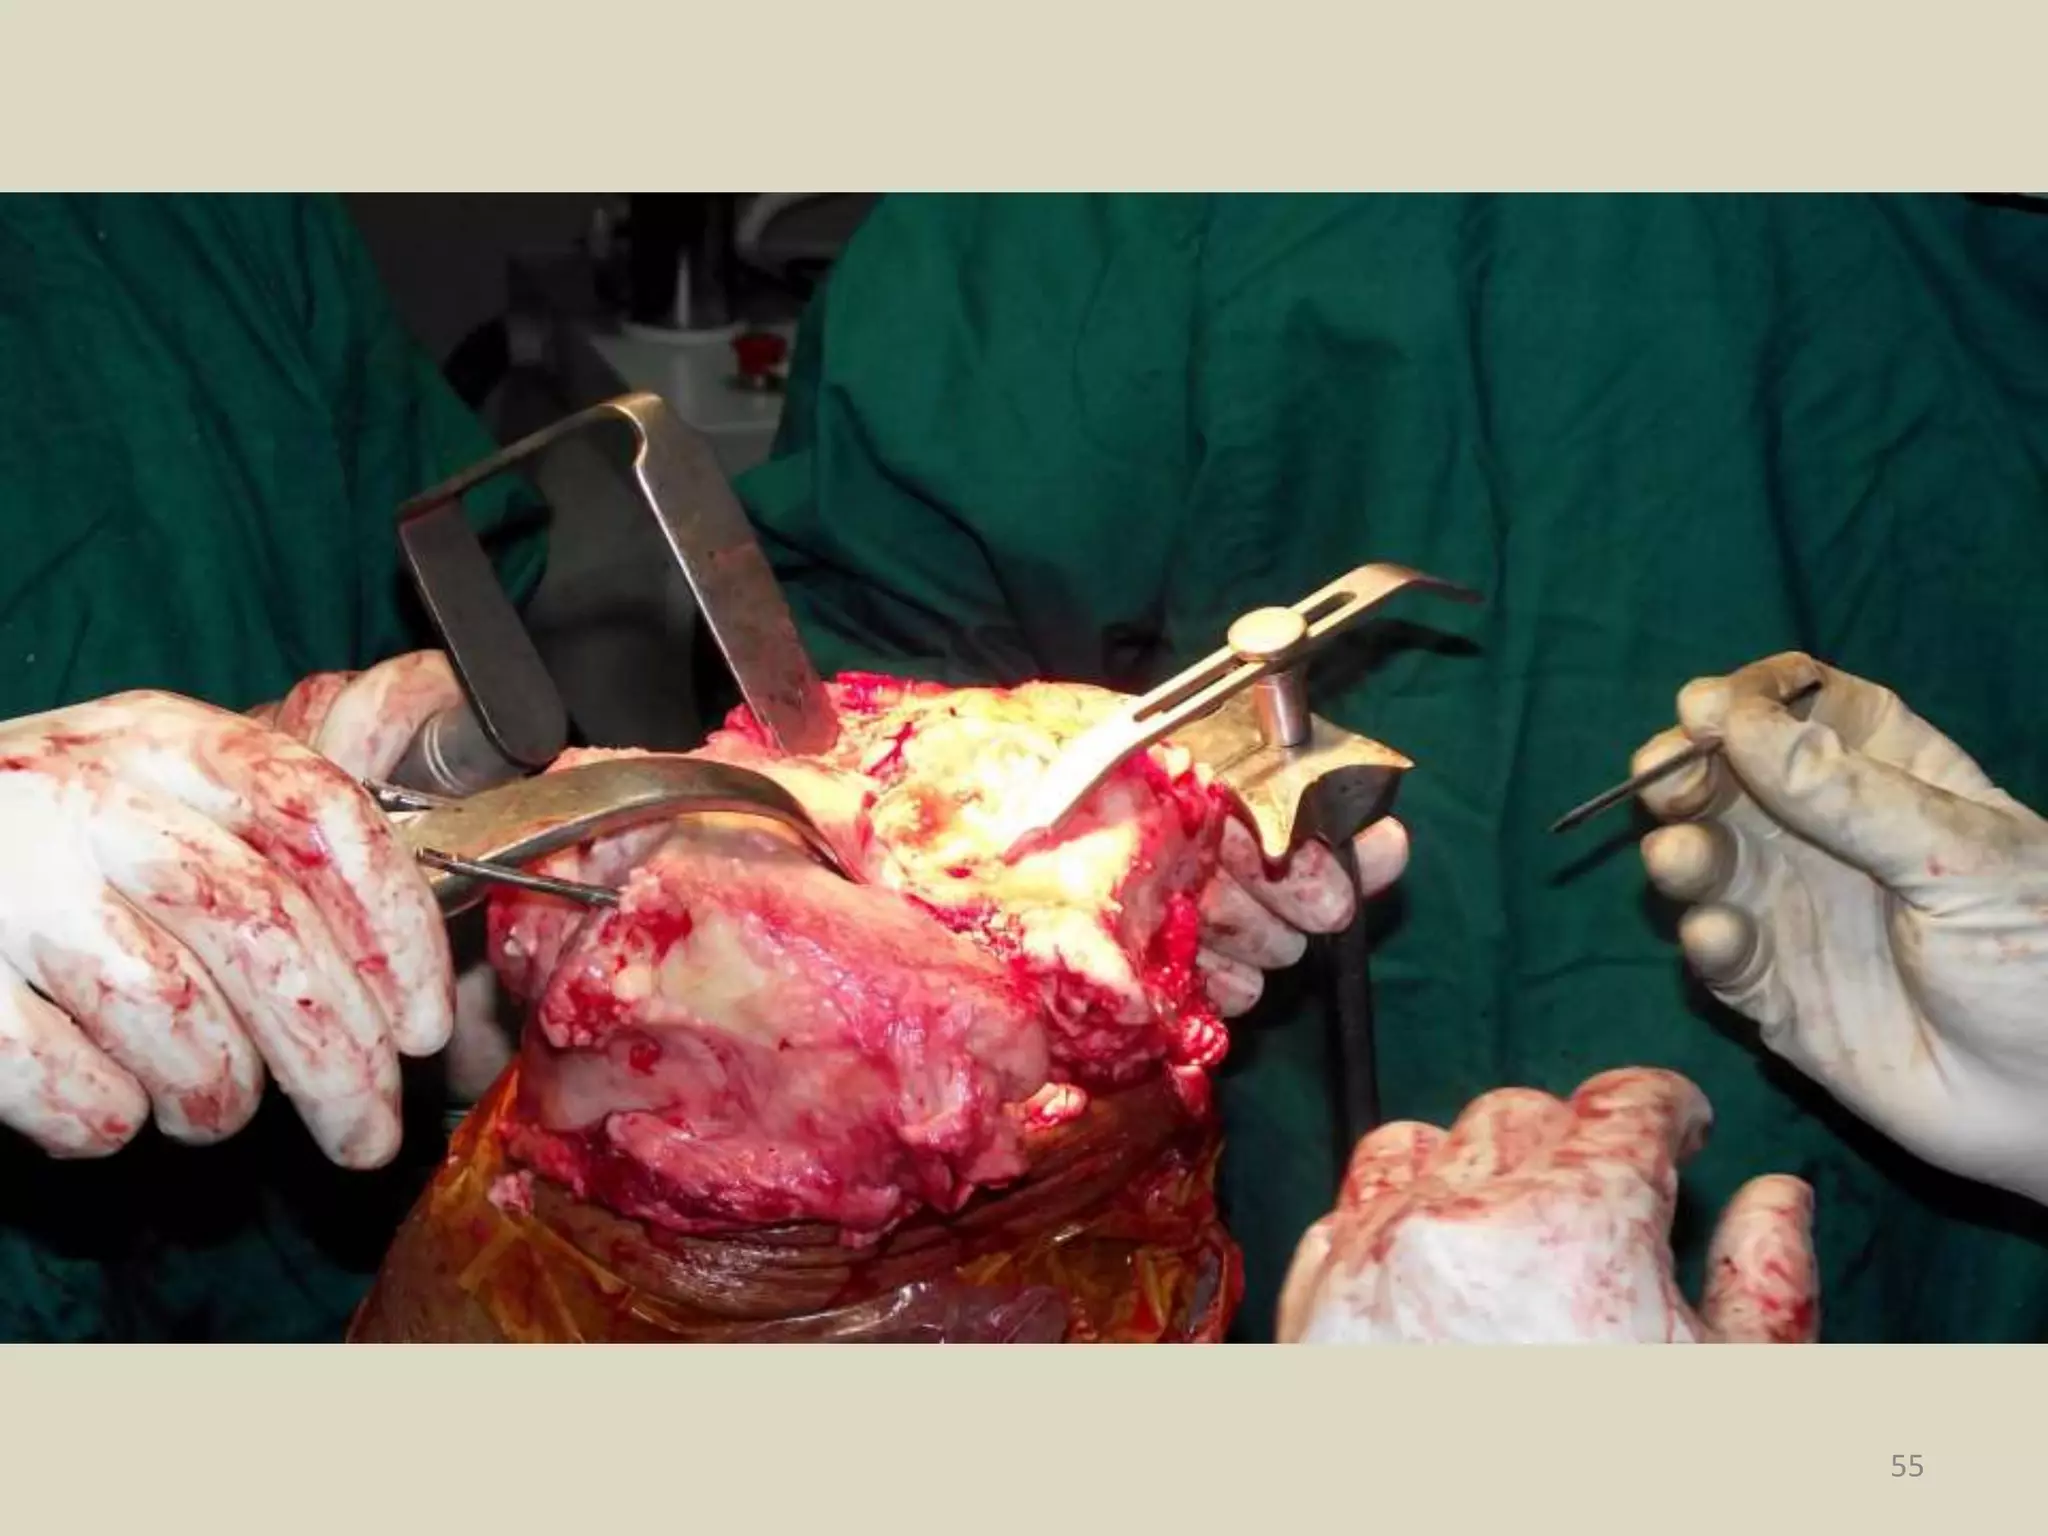

Total Knee

Arthroplasty

Indications for Total Knee

Joint Replacement

The main indication for Total Knee

Arthroplasty is for relief of pain associated

with arthritis of the knee in patients who

have failed non operative treatments.

(American Academy of Orthopedics)